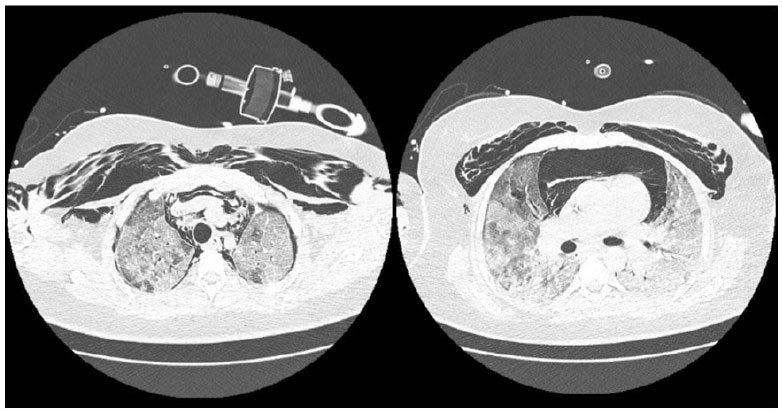

Após o início de VM invasiva, apresentou assincronias frequentes, dificuldade de manter parâmetros VM protetora, com necessidade de ajustes frequentes no ventilador e de associar sedativos em altas doses e bloqueador neuromuscular (fez uso de midazolam, propofol, fentanil e pancurônio). Exame de imagem após intubação orotraqueal, mostrava cânula endotraqueal bem-posicionada, opacidades parenquimatosas difusas, cateter venoso central à direita e sem sinais de pneumotórax (vide figura A). Entretanto, no dia 05/04/21 paciente apresentou ao exame físico enfisema subcutâneo extenso em região torácica e cervical, realizou exames de imagem que evidenciaram extenso enfisema subcutâneo e moderado pneumomediastino (vide figuras B e C). Discutido caso com equipe de cirurgia torácica que optou por manter tratamento conservador e não realizar procedimentos invasivos, como drenagem de subcutâneo.

Paciente evoluiu com hipoxemia e índice de oxigenação compatível com SDRA grave (IOX < 150), realizado pronação de paciente no dia 06/04/21 às 12:30 com objetivo de promover recrutamento alveolar e de melhorar oxigenação. Infelizmente, a paciente evoluiu com hipoxemia refratária e veio a óbito às 4h16 do dia 07/04/2021.